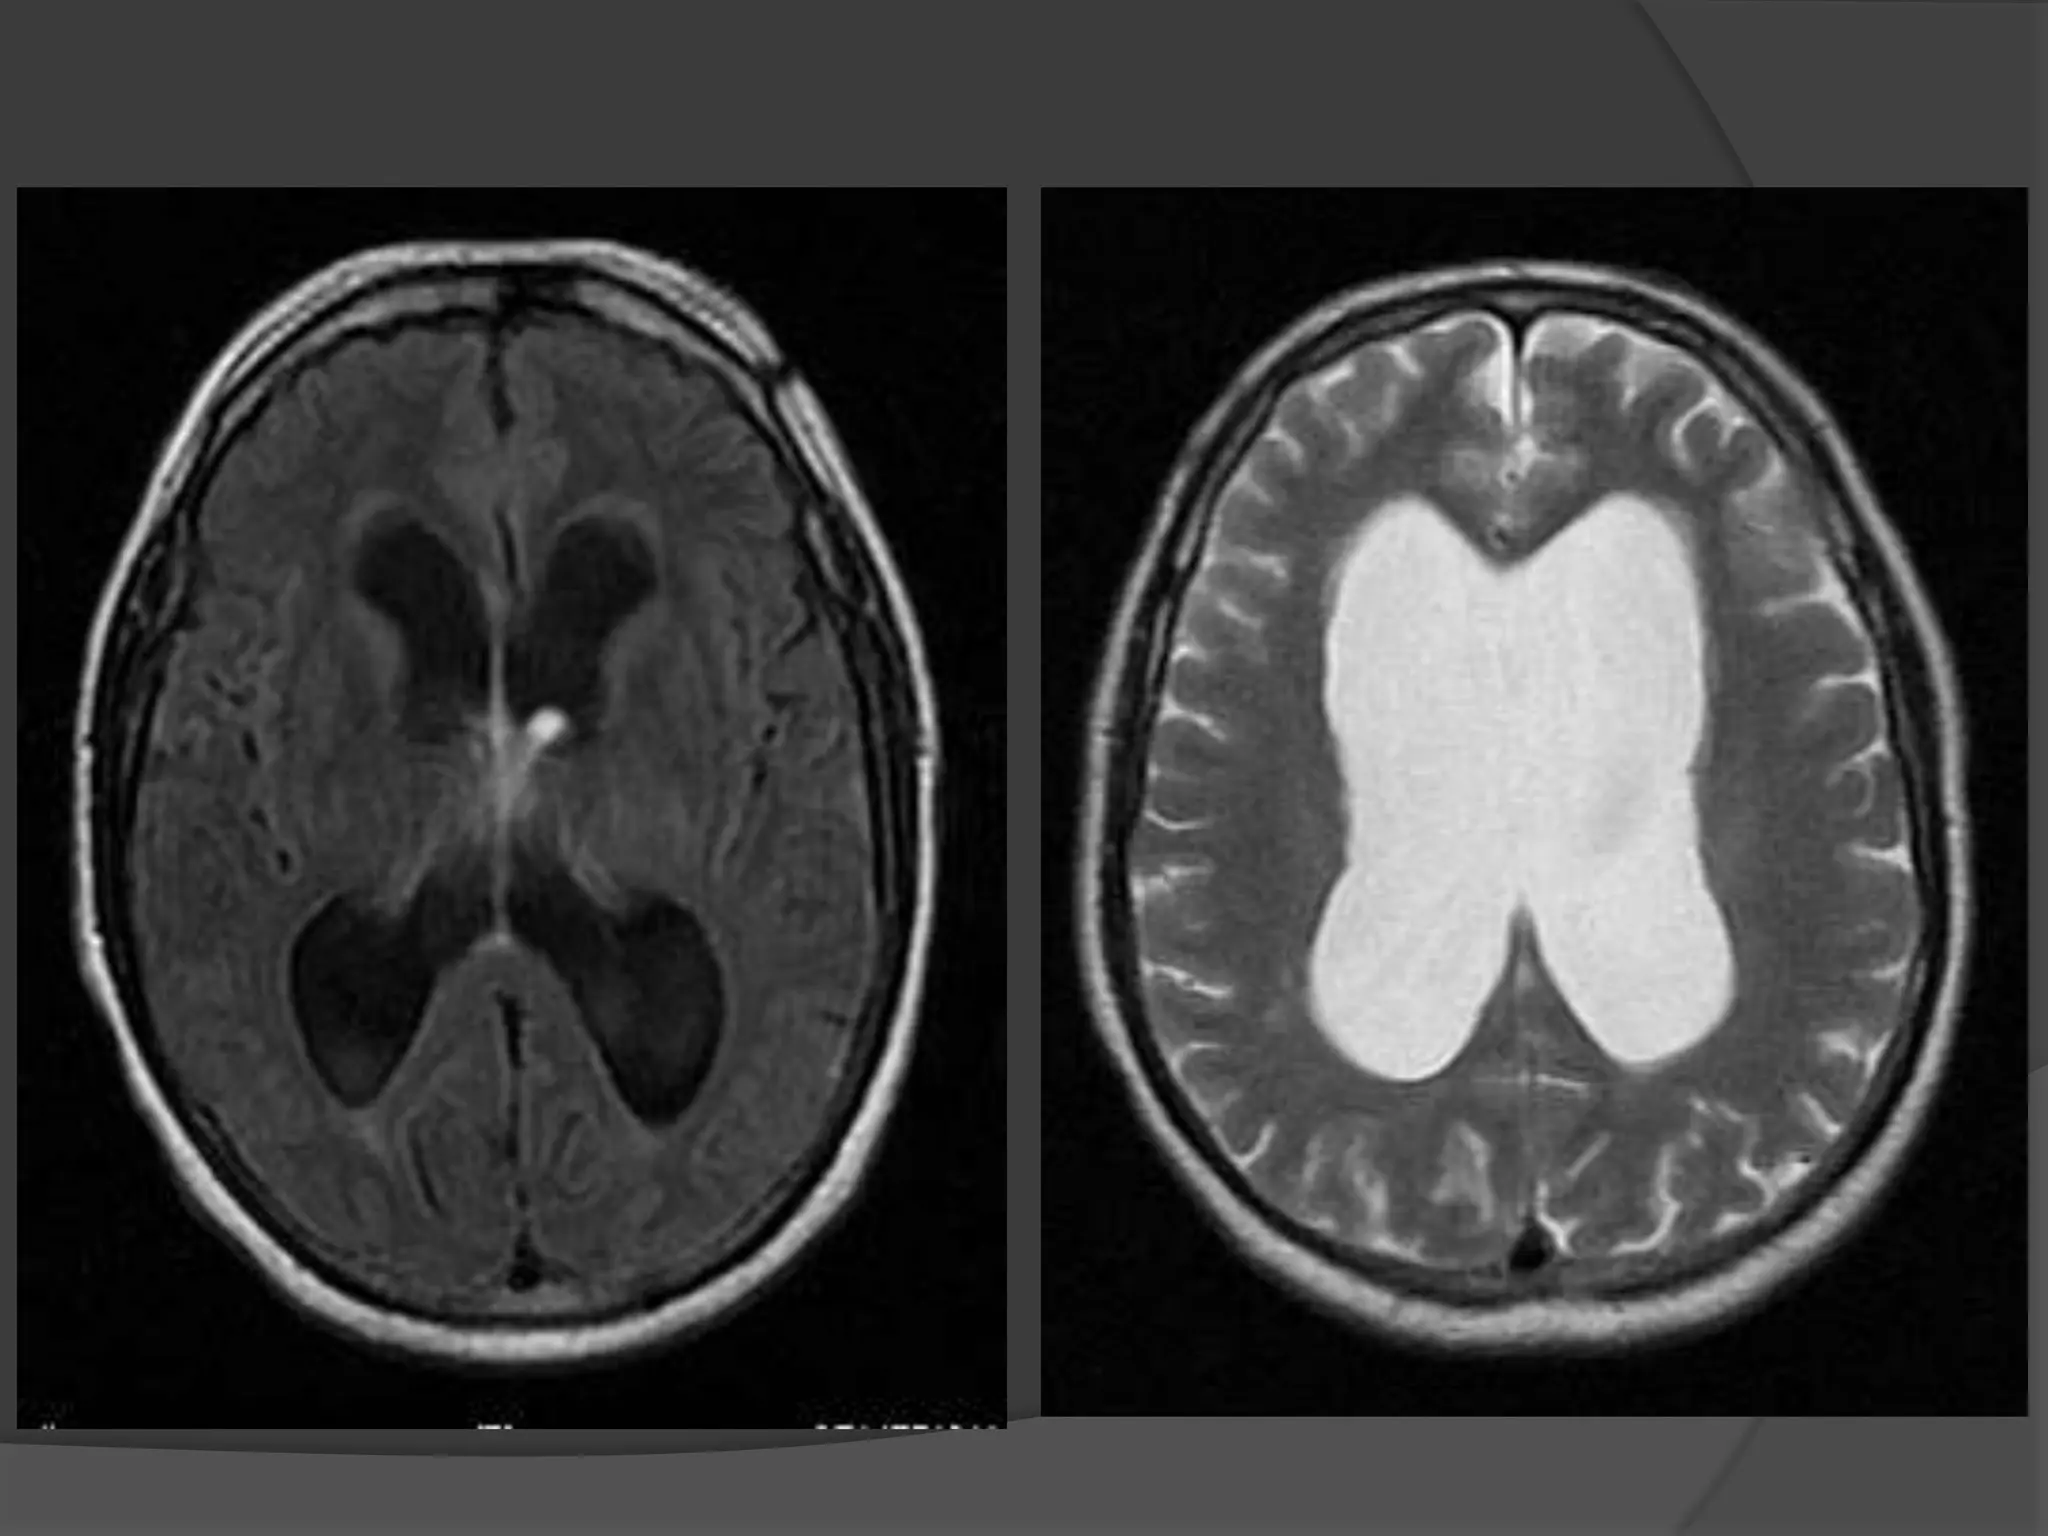

Fluid Attenuated Inversion Recovery

(FLAIR)



Special type of MRI scan

T1 image is inverted & added to

the T2 image

Contrast between grey & white

matter is doubled & the normal

CSF signal is suppressed.

Special indications

1.

To detect Sclerosis of

hippocampus in Temporal lobe

epilepsy.

2.

To Localize the areas of

abnormal metabolism in

degenerative neurological

diseases.